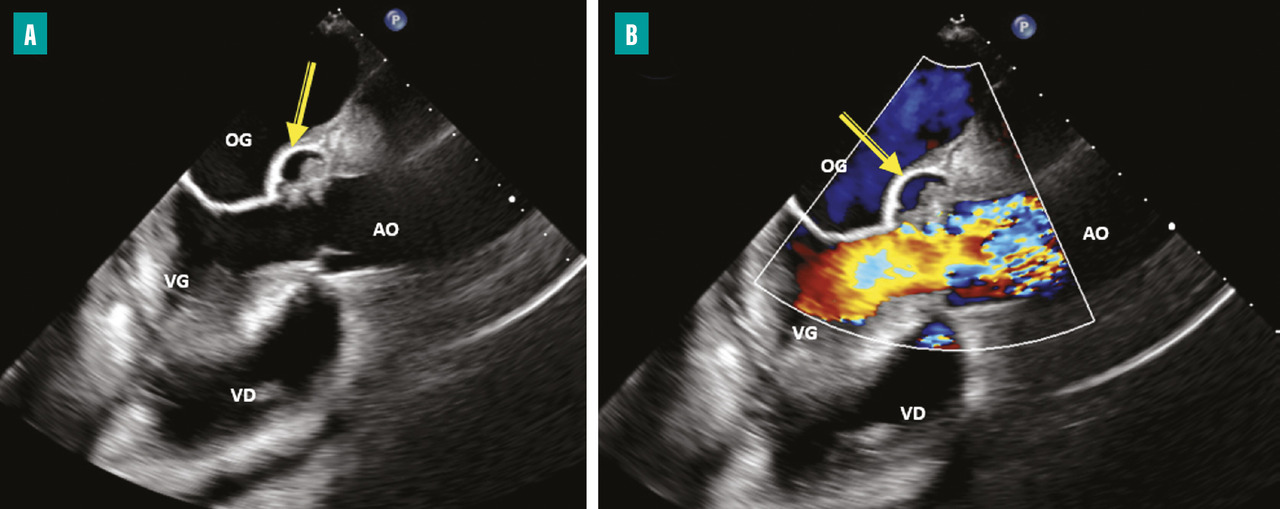

L’apparition à l’échographie cardiaque d’un abcès périvalvulaire ou périprothétique aortique (fig. 3 ) ou mitral est une complication grave de l’EI. L’abcès est plus fréquent dans les EI sur prothèses valvulaires (50 à 80 % contre 10 à 40 % sur valves natives). L’ETO est plus sensible que l’ETT pour ce diagnostic (notamment pour les localisations postérieures)2 et le scanner cardiaque est très performant pour la recherche d’abcès sur prothèse. La détersion de l’abcès peut être à l’origine de fistules entre les différentes cavités cardiaques (fig. 4 ). La fistulisation se fait le plus souvent dans la chambre de chasse du ventricule gauche. Les fistules intracardiaques dans l’oreillette gauche ou droite peuvent être à l’origine d’un tableau d’insuffisance cardiaque et compliquent le geste chirurgical.

– à l’évolution locale de l’infection par une extension périvalvulaire ou périprothétique des lésions et la formation d’un abcès (fig. 3 ) ou d’une fistule intracardiaque (fig. 4 ).